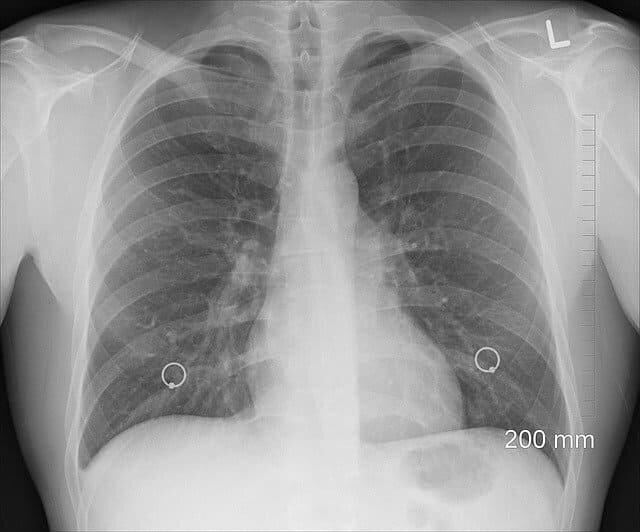

Насколько здоровы ваши легкие - измерьте объем легких самостоятельно

Вы можете быстро и легко проверить, насколько эффективны ваши собственные легкие в домашних условиях - даже без прохождения теста производительности у врача.